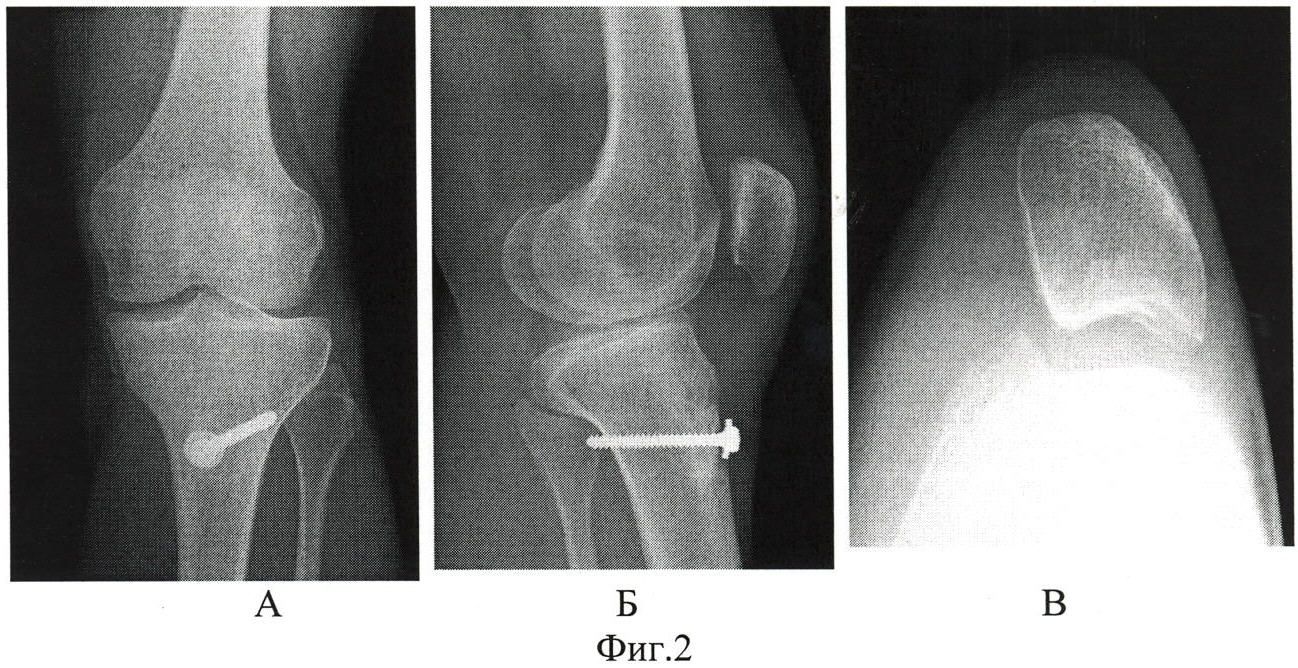

На рентгенограмме показан перелом тела надколенника без смещения.

На рентгенограмме продемонстрирован перелом нижнего полюса надколенника.

Перелом надколенника слева со смещением отломков. Необходима операция.

Краевой перелом надколенника, хорошо видимый на аксиальной рентгенограмме.

Фиксация перелома надколенника винтами.

Наиболее распространённый способ фиксации – это остеосинтез по Веберу, хирургу, который придумал эту операцию. При этой операции для фиксации используются спицы и проволока (продемонстрировано на схеме ниже).

Рентгенограммы после остеосинтеза надколенника по Веберу.